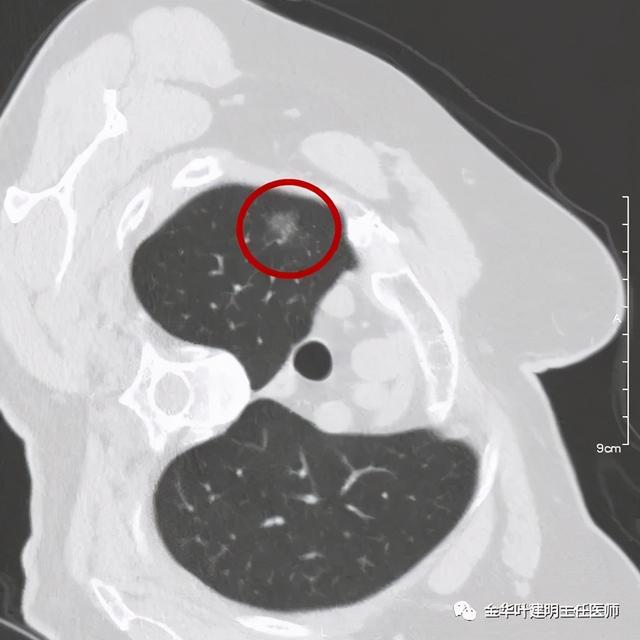

患者为女性 , 今年76岁 , 平时体质甚好 , 家务及地里劳动都胜任 , 头发仍乌黑(我自己倒有一半白发了) 。 肺功能与血气分析正常 。 CT检查图像如下:

可见右肺上叶混合磨玻璃结节 , 有明显分叶征 , 瘤肺边界虽然欠清楚 , 但轮廓比较清晰 。 看着也许会考虑炎性 , 但总觉得其比较僵硬 , 看去不舒服 。 这种病灶一是如果持续存在就极可能是肺癌 , 二是靶扫描显示更清晰的细节 , 如果瘤肺边界还是清楚的 , 也基本是肺癌 。 我们回顾发现其于2019年3月在我们医院做过CT平扫 , 当时报告如下: